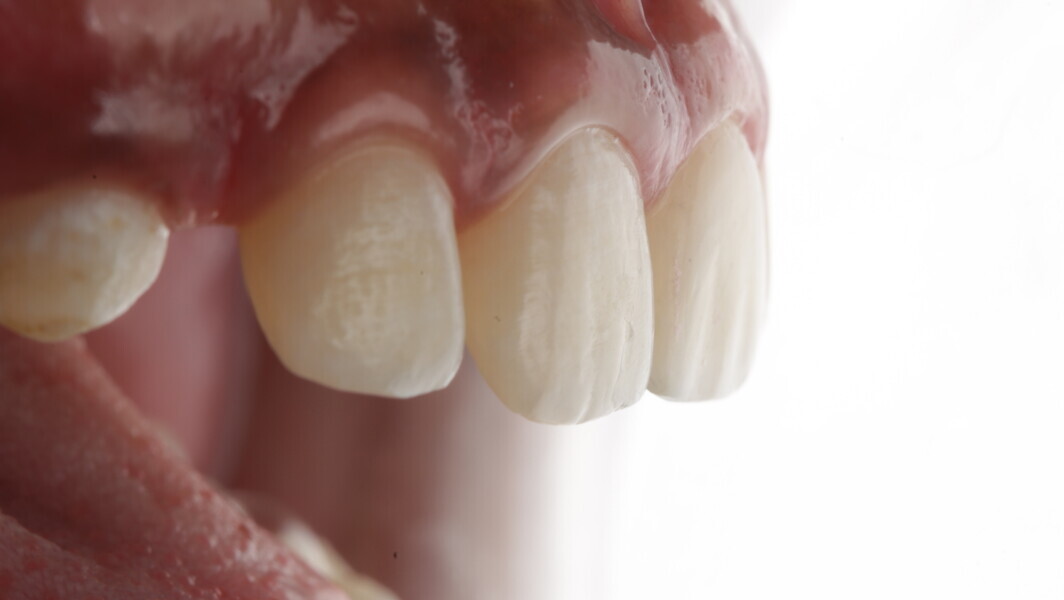

Fig 31-41: Polishing protocol and post-op

The article demonstrates how using the right protocols and armamentarium for composite materials can give life-like results in a short time in a minimally invasive way. No single layering technique can ensure a 100% success rate. Regardless of the technique, establishing good secondary and tertiary anatomy and thorough polishing are the key steps that make a restoration look more natural. Composite is the perfect material for allowing correction of mistakes or improvement.